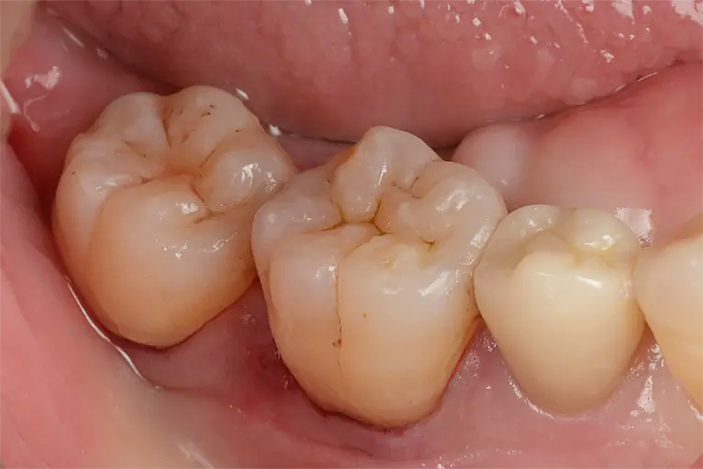

Case1

術前

ラバーダム防湿

術後

| 治療名 | ダイレクトボンディング |

|---|---|

| 治療説明 | 古い銀歯の下で虫歯が発生したため、ダイレクトボンディングを行いました。古い銀歯を除去し、ラバーダムを装着し、う蝕を除去してレジンを充填し、見た目と機能を回復しました。 |

| 治療回数・期間 | 1回 |

| 副作用とリスク | 知覚過敏症状が生じる恐れがあります。レジンが破折歯修復が必要となることがあります。 |

| 料金(税込) | 55,000円(自費) |